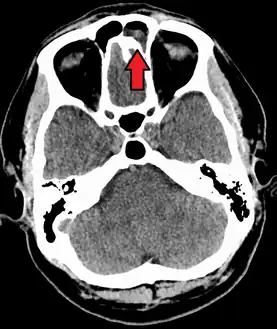

A CT scan showing sinusitis of the ethmoid sinus

For sinusitis lasting more than 12 weeks, a CT scan is recommended.[54] On a CT scan, acute sinus secretions have a radiodensity of 10 to 25 Hounsfield units (HU), but in a more chronic state they become more viscous, with a radiodensity of 30 to 60 HU.[56]